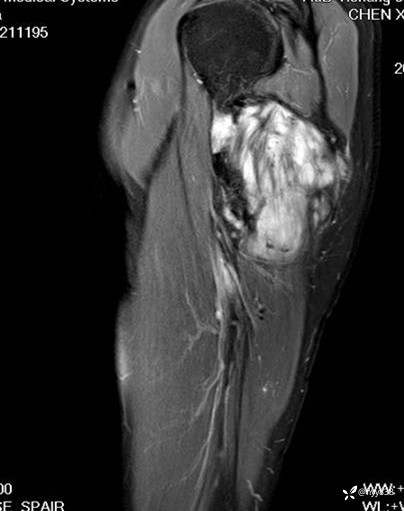

MRI AXI T1WI+T2WIfs

AXI T1WI+T2WIfs